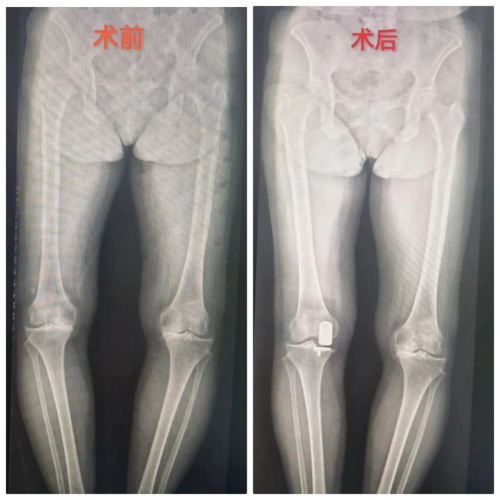

近年来,随着微创外科技术的发展和保膝理念的盛行,单髁置换术(UKA)在国内逐渐推广,立博体育 运动医疗关节骨病科自开展膝关节单髁置换以来,为多位老年患者解决了行走之痛。4月1日上午,行“膝关节置换术”术后第二天的彭奶奶一边在病房走廊上练习行走,一边向旁边好奇的老病友介绍自己手术后的情况。

运动医疗关节骨病科主任李良军介绍:“膝关节作为人体结构最复杂的关节,又是负重关节,容易患上骨性关节炎,以往大多采用的是一刀切的全膝关节置换术,但实际上许多膝关节骨性关节炎患者只是单一间室局部病变,也就是只有一部分产生了病变。韧带结构良好,不需要全膝置换,单髁置换应运而生。所谓单髁置换,就是精准置换产生病变的部位,最大限度保留膝关节功能和本体感觉。单髁置换相比全膝置换有几大优势,主要体现在:切口小,出血量少,可以最大化地保留正常组织,术后恢复快,本体感觉好,最重要的是更具人性化。当然,如果是整个膝关节都出了问题,还是首选全膝关节置换了。”